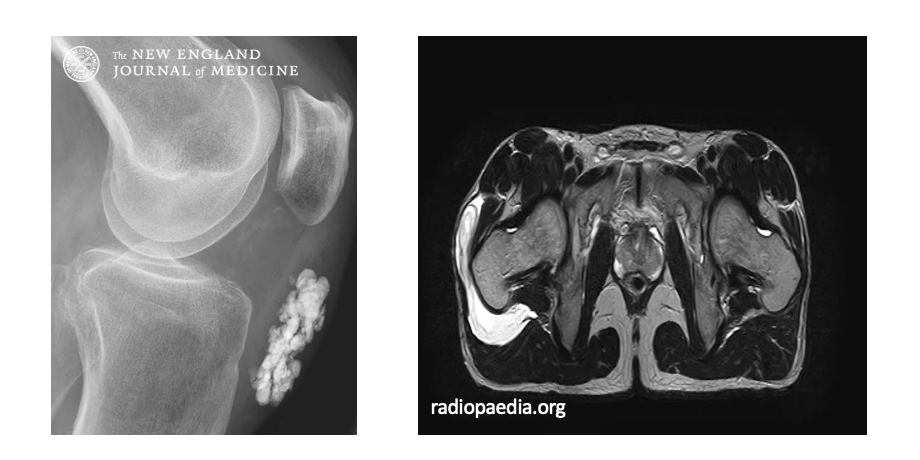

# MSS Inflammatory Arthropathies What is Crystalline arthritis/ gout? ## Footnote *LOB:Compare rheumatoid arthritis with other common inflammatory joint diseases such as gout and psoriatic arthritis

Seronegative High uric acid Initially monoarthritic – can become polyarticular Tophi on physical examination urate crystals in synovial fluids

# MSS Inflammatory Arthropathies What is crystalline arthritis/ psuedo gout? ## Footnote *LOB:Compare rheumatoid arthritis with other common inflammatory joint diseases such as gout and psoriatic arthritis

Calcium pyrophosphate crystals in synovial fluids Neutrophils phagocytose Pro-inflammatory Chondrocalcinosis on radiographs Pc acute monoarthritis Risk: Trauma, Age, Metabolism, Genetic